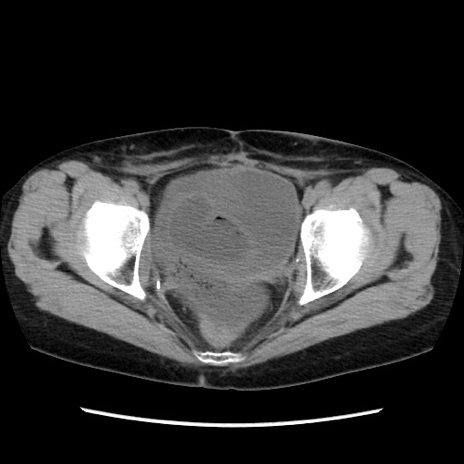

症例32(横断像)

【症例】40歳代 女性

【主訴】上腹部痛、嘔気・嘔吐

【現病歴】約9時間前頃から急に上腹部痛、嘔気、嘔吐が出現。改善しないため救急要請。

【既往歴】子宮頚癌(広汎子宮全摘術、放射線療法)、腸閉塞